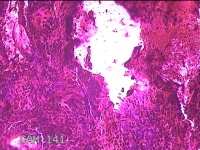

左侧鼻腔新生物

性别

女

年龄

43岁

临床诊断

1.慢性鼻窦炎 2.鼻息肉 3.鼻中隔偏曲 4.鼻腔粘连 5.变应性鼻炎

一般病史

鼻塞、脓涕3月余。’

标本名称

大体所见

灰白暗红色不规则肿物1.3x0.3x0.2cm一个,表面糜烂,内有少许骨质。

图1